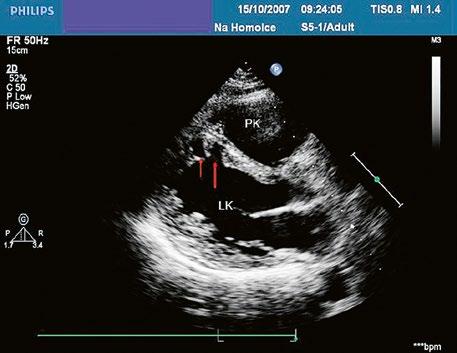

Obr. 45.14 TTE, čtyřdutinová apikální projekce. Kompletní atrioventrikulární septální defekt je označen křížky, představuje komunikaci mezi oběma síněmi i komorami se společnou atrioventrikulární chlopní (AVch)

LK – levá komora, LS – levá síň, PK – pravá komora, PS – pravá síň